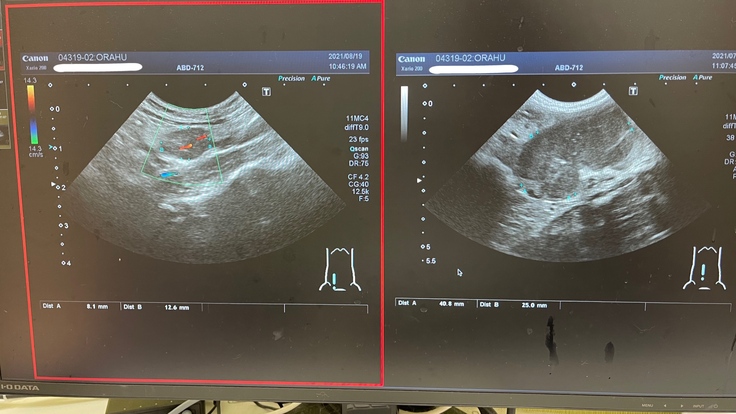

A病院での血液検査を見てもらい、超音波検査を行いました。

熱はありませんでしたが、4cm程のしこりがあり腹水が少し溜まっていて、FIP混合タイプだろうと言われました。

8月19日

定期検査(投薬を始めて2週間後)です。

4cm程あった肉芽腫が、1.2cmとすごく小さくなっていました。

大きかった肉芽腫がたった2週間でこんなに小さくなることに驚きました。

オラフの食欲も戻ってきて、だいぶ元気にもなってきました。

84日間新薬をのませて治してあげたいという気持ちがさらに強くなりました。

8月19日の肉芽腫 7月29日の肉芽腫